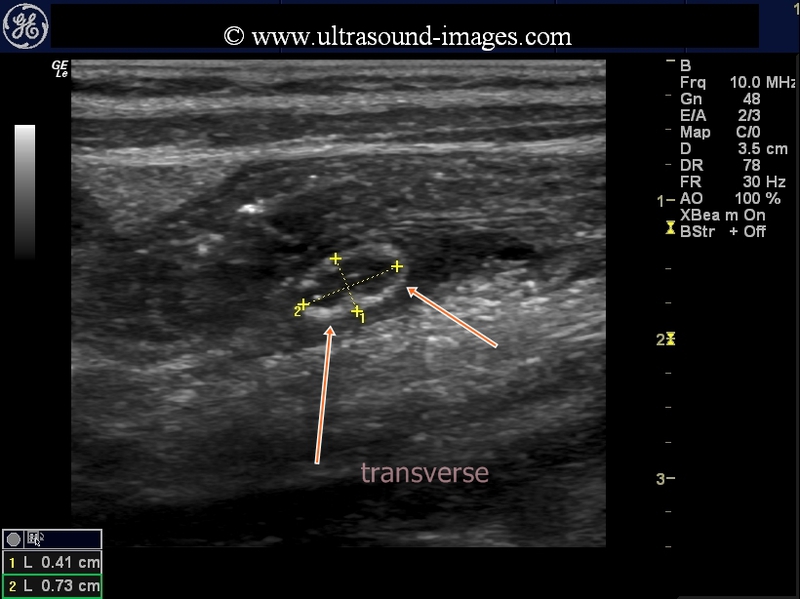

Cross section (transverse section)- Markedly vascular appendix

This male child has a markedly vascular and swollen appendix at 5 to 7 mm. width. Using graded compression it was possible to visualize the acutely inflamed appendix in its entirety. These ultrasound and Power Doppler images show a typical case of acute appendicitis. The Power Doppler ultrasound image at bottom shows a literal ring of fire within the cross section of the inflamed appenidx. Such a case may or may not respond to conservative medical treatment and surgery may be the final option. Fortunately for the patient there is no evidence of impending rupture of the appendix at the present stage. There is no evidence of collection of fluid (phlegmon) around the appendix.